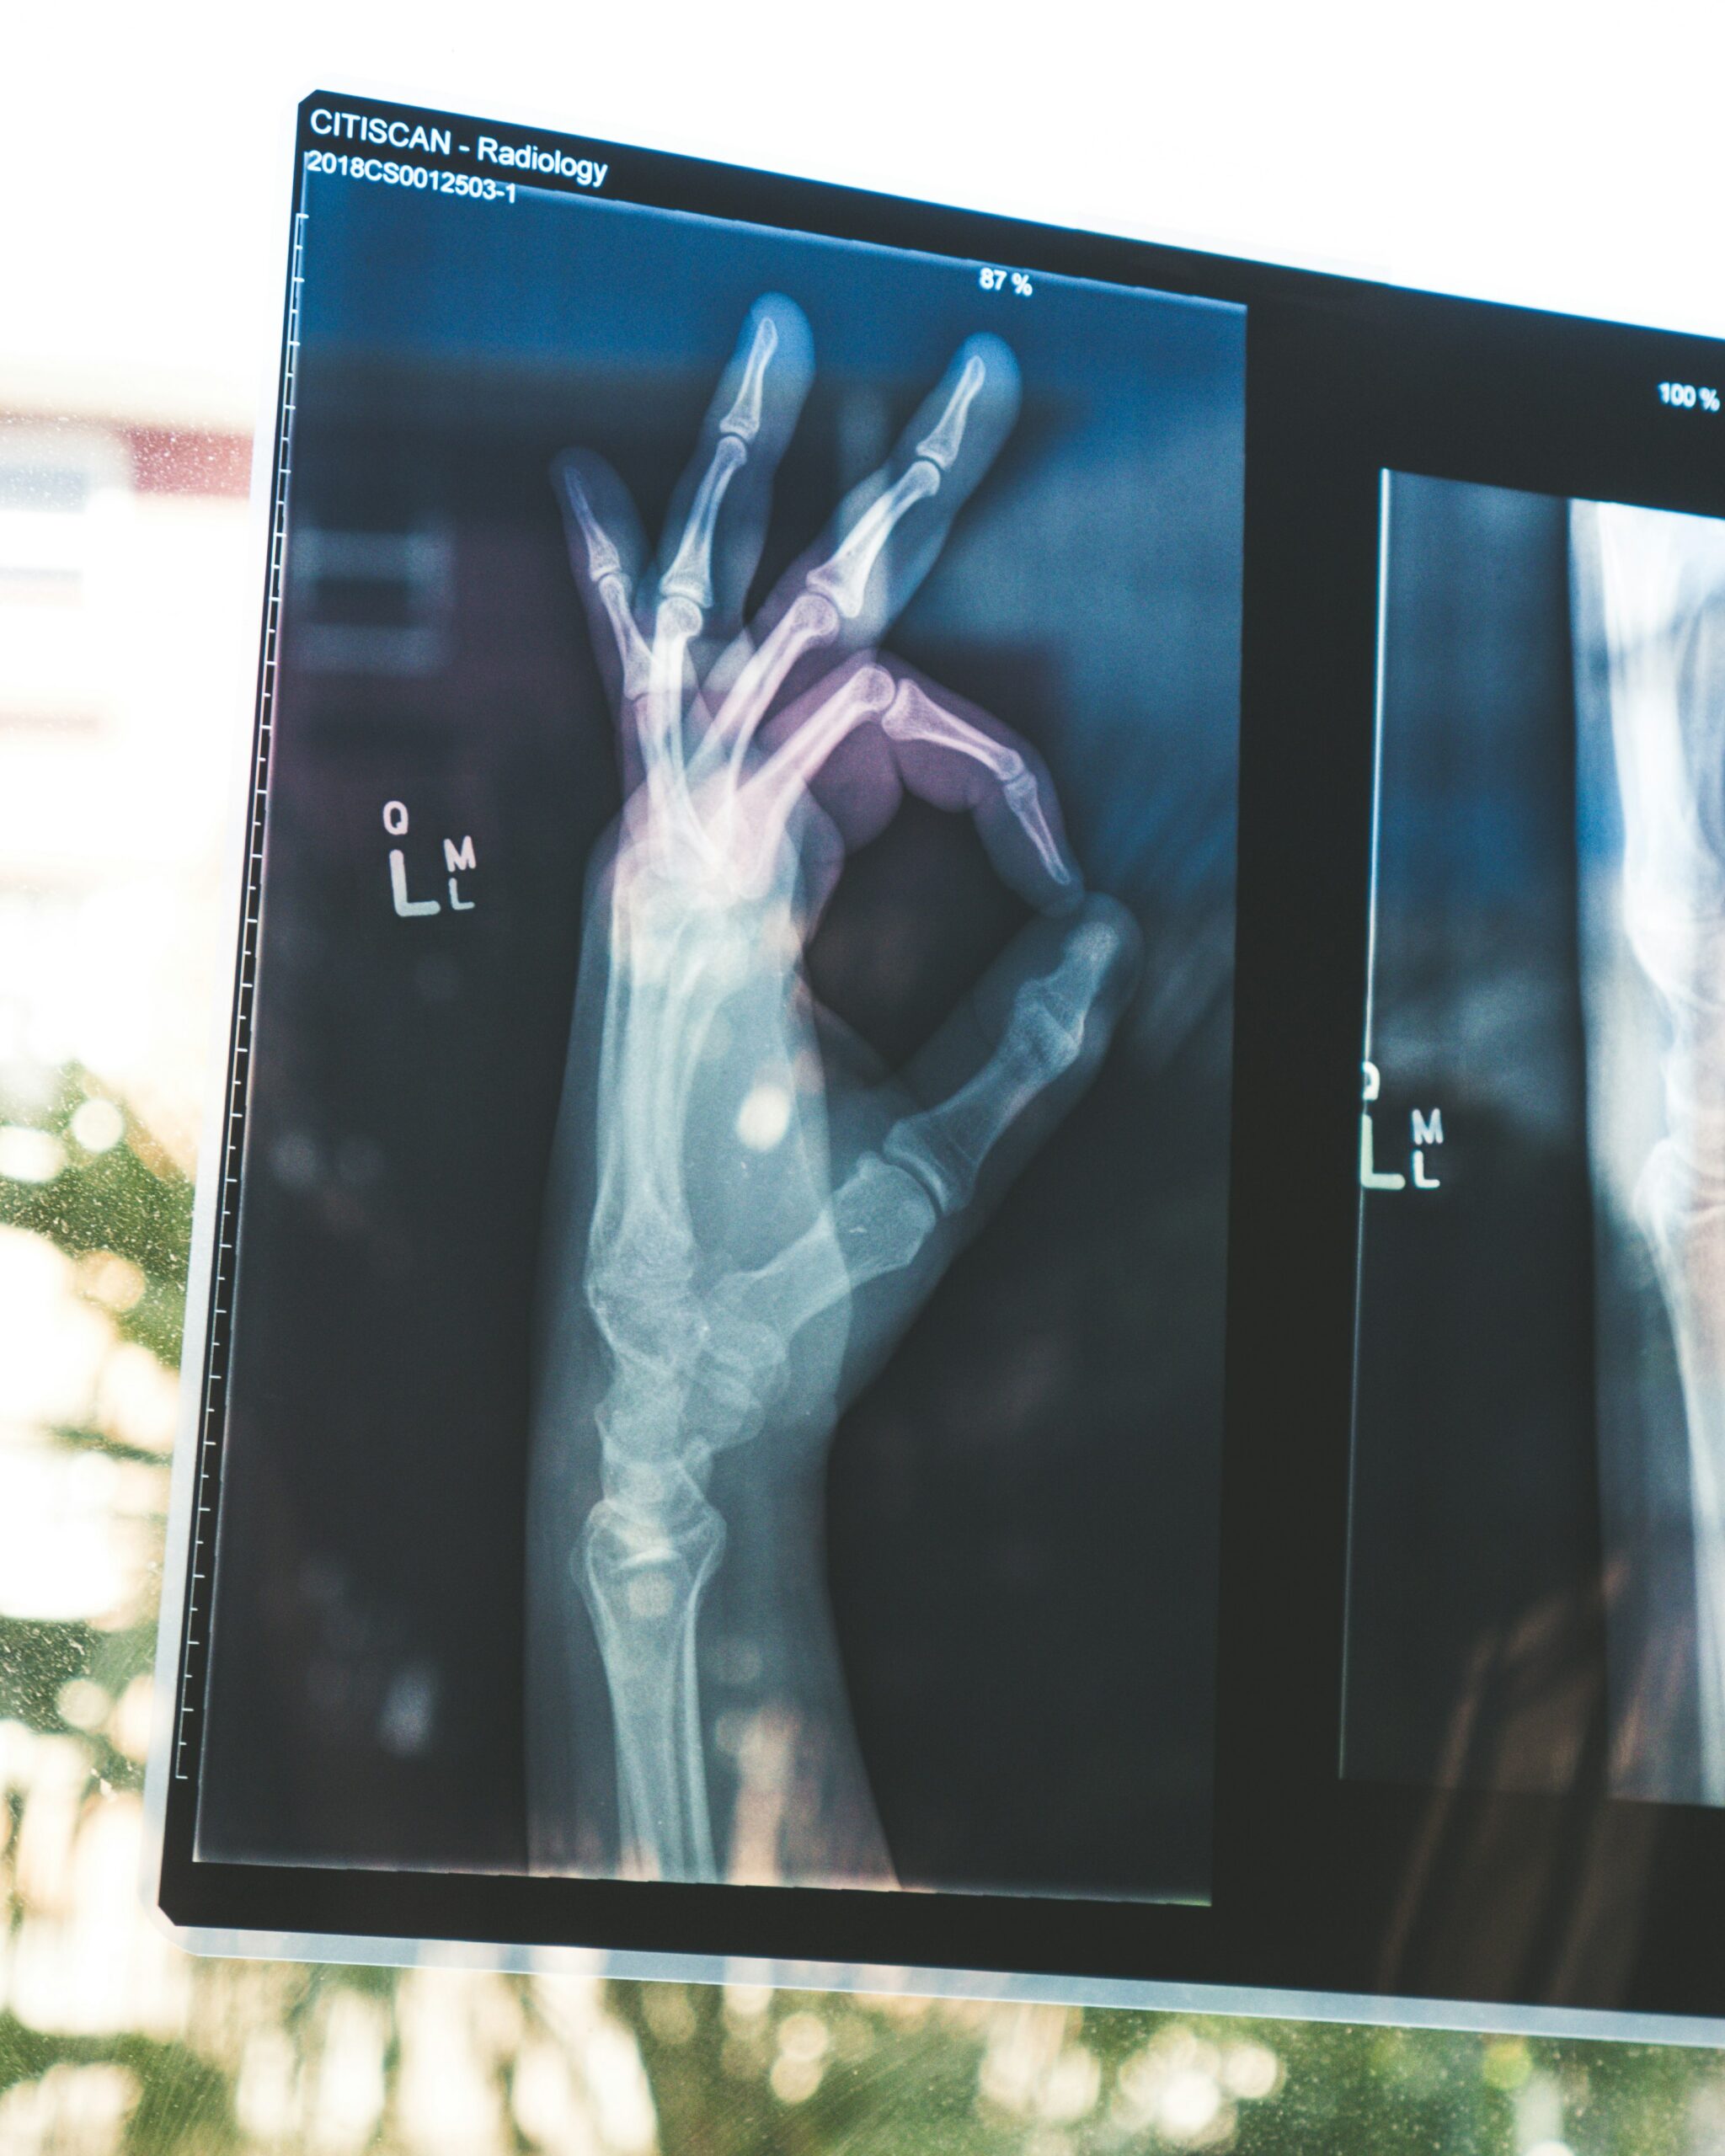

Científicos de la Universidad Politécnica de Hong Kong crearon “X‑Wear”, una tela flexible e inorgánica que detecta rayos X con 10 veces más brillo que versiones previas. Promete escáneres portátiles y protección contra radiación, ideal para salud en movimiento.

Metatela flexible para rayos X podría transformar la tecnología wearable